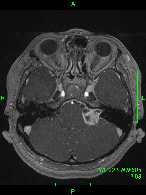

症例1) 65歳男性、頭蓋底部巨大髄膜腫、外科手術のみ

<画像所見>

巨大脳腫瘍を認める。

錐体斜台部巨大髄膜腫を認め、

神経や血管を巻き込んでいる。